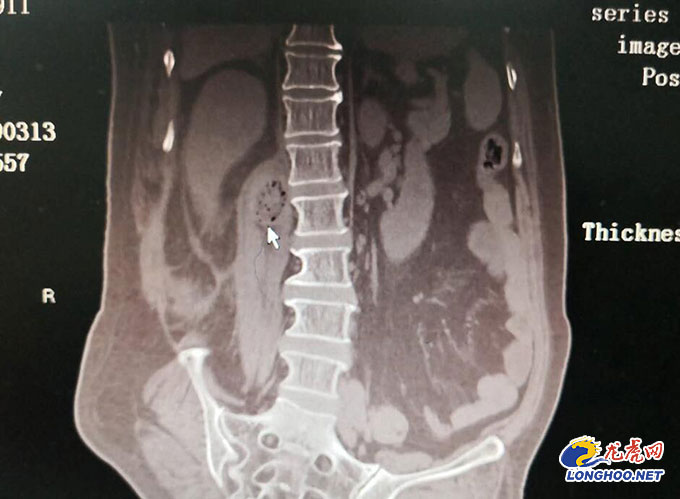

时女士的病情初步考虑为神经鞘瘤可能,肿瘤起源于椎间孔神经根可能性大。由于肿瘤较大,有5cm*4cm*4cm大小,而且位置较深,位于肾脏及腰椎之间,手术风险确实很大。神经外科主任樊友武教授、吴有志副主任医师等专家充分地讨论了时女士的病情,并制定了完善的手术方案。

术中,专家们在显微镜下经椎旁正中入路逐渐暴露椎旁深部肿瘤及其包膜,小心保护外侧的肾周筋膜,内侧见肿瘤起源于椎间孔神经根,完整切除肿瘤及其包膜。术后,时女士的疼痛症状完全消失,走路完全不受影响,影像学检查也证实肿瘤完全切除,而且病理也确诊是个良性的神经鞘瘤时,时女士揪着的心也落地了,最后经术后一周的观察治疗,时女士开心健康的出院回家了。